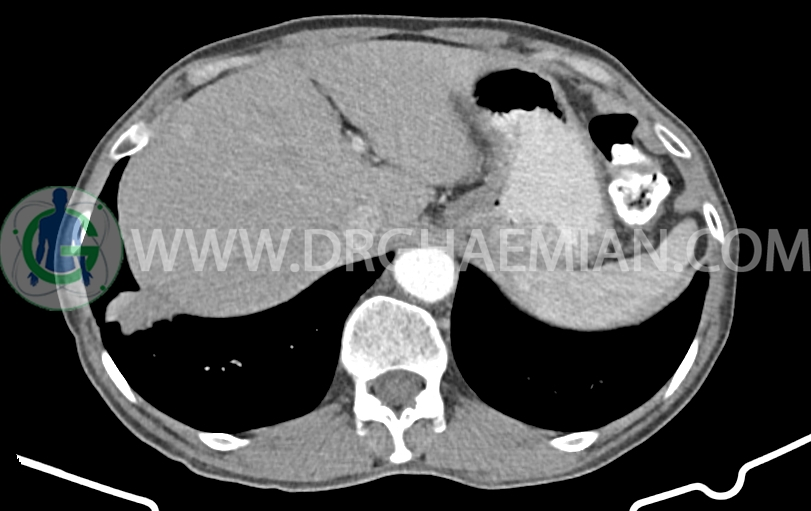

لنف نود به ابعاد mm 14×10 در مجاورت origin SMA دیده می شود. (بدون تغییر نسبت به سی تی اسکن قبلی)

شواهد جراحی ویپل به صورت partial pancratectomy و کوله سیستکتومی و همچنین گاستروژژنوستومی و پانکراتیکوژژنوستومی – هپاتوژژنوستومی مشهود است .

کانون کلسیفیه کوچک فاقد اهمیت بالینی در لوب راست کبد رویت شد

پنوموبینی در لوب چپ کبد مشهود است.